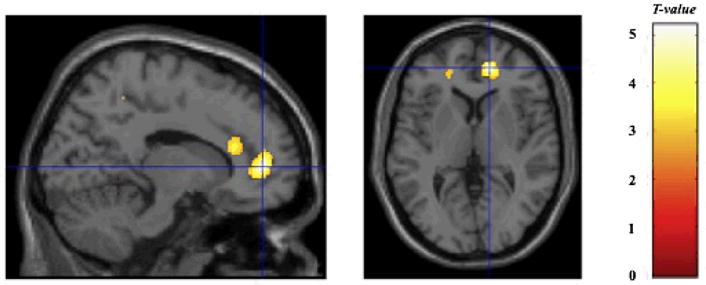

The most prominent finding was a significant reduction in GMV in the right medial frontal gyrus (medial prefrontal cortex, MPFC) in individuals exposed to CP (BA 10; Talairach’s coordinates x= 14, y= 47, z= 1, cluster size = 402, P = 0.037, corrected cluster level) (Fig. 1). A 19.1% lower average GMV was found in these regions of the CP subjects than in healthy controls.

Fig. 1.

Significant differences between corporal punishment (CP) subjects and controls. Significantly lower gray-matter densities in CP subjects were measured in the right medial frontal gyrus (medial prefrontal cortex, BA10). Crosshairs placed at x= 14, y= 47, z= 1, the right medial prefrontal cortex. Color scale: 0–5 represent t-values.

Using lower criteria for statistical significance revealed 14.5% reduction in GMV in the left medial frontal gyrus (dorsolateral prefrontal cortex; DLPFC) (BA 9; Talairach’s coordinates x= 10, y= 40, z= 20, cluster size = 283, P = 0.015, uncorrected cluster level) and 16.9% reduction in GMV in the right anterior cingulate gyrus (BA 24; Talairach’s coordinates x= 10, y= 30, z= 15, cluster size = 124, P < 0.001, uncorrected voxel level). No other areas of reduction were found with a corrected cluster probability value that approached significance.